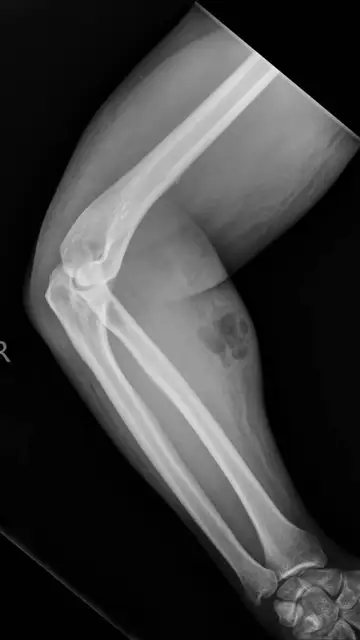

En realidad, el hombre tenía los dolores desde hace más de un año, pero eso no era todo. Los médicos vieron que su brazo presentaba un aspecto extraño y no era para menos. Desde hacía 18 meses se estaba inyectando su propio semen con una aguja que decidió comprar a través de Internet. Así lo publica 'Irish Medical Journal'.

El hombre creía que con este particular remedio iba a calmar su dolor de espalda, pero lo único que hizo fue crearse complicaciones en su brazo. Al inyectarse el semen lo que había hecho también es introducir aire debajo de la piel, por lo que tuvo que ser intervenido.